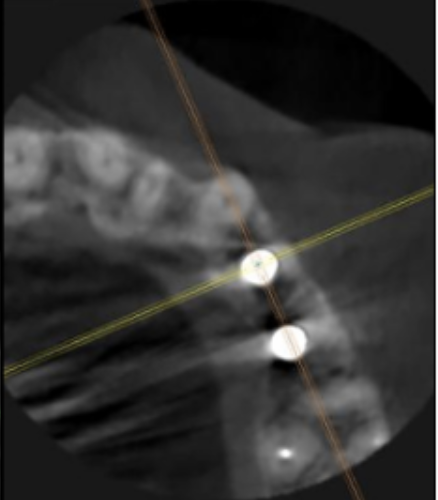

サージカルガイドの作成

インプラント埋入前のCTによる確認